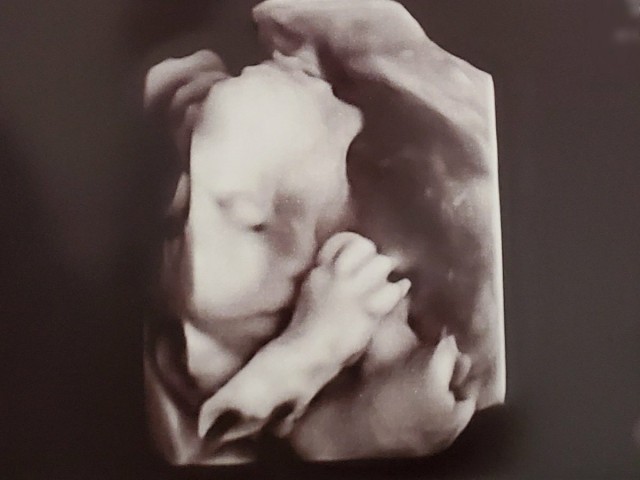

体重管理 妊娠27週間 糖負荷検査2回目もダメだった?次回から内科と産科通いになって様子みるらしい。産科の先生は体重全然増えてないし(つわりが完全に終わらなくて食欲無い)体質かな〜って言ってたけど、内科ではなんて言われるのかな…。 お腹の子は元気のよう、エコーで見たら娘にそっくりだった。